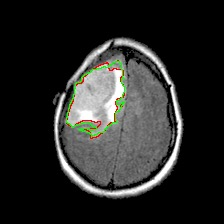

Neural processes have recently emerged as a class of powerful neural latent variable models that combine the strengths of neural networks and stochastic processes. As they can encode contextual data in the network's function space, they offer a new way to model task relatedness in multi-task learning. To study its potential, we develop multi-task neural processes, a new variant of neural processes for multi-task learning. In particular, we propose to explore transferable knowledge from related tasks in the function space to provide inductive bias for improving each individual task. To do so, we derive the function priors in a hierarchical Bayesian inference framework, which enables each task to incorporate the shared knowledge provided by related tasks into its context of the prediction function. Our multi-task neural processes methodologically expand the scope of vanilla neural processes and provide a new way of exploring task relatedness in function spaces for multi-task learning. The proposed multi-task neural processes are capable of learning multiple tasks with limited labeled data and in the presence of domain shift. We perform extensive experimental evaluations on several benchmarks for the multi-task regression and classification tasks. The results demonstrate the effectiveness of multi-task neural processes in transferring useful knowledge among tasks for multi-task learning and superior performance in multi-task classification and brain image segmentation.